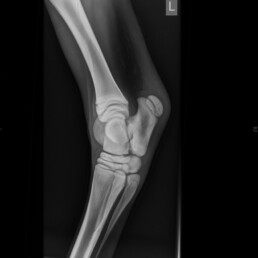

Nach vier Wochen wurden Kontrollaufnahmen der Gliedmaßen angefertigt. Hier ist im Vergleich zu den vorherigen Aufnahmen ein deutliches Voranschreiten der Ossifikation zu erkennen, jedoch ist die Ossifikation weiterhin unvollständig (Abb. 3 und Abb. 4). An der rechten Vordergliedmaße besteht zudem ein Carpus valgus mit einer Achsenabweichung von 10°.

Abb. 3 Tarsus links 90°: Hypoplastische Ossifikation Grad IV

Abb. 4 Carpus links 0°: Hypoplastische Ossifikation Grad IV